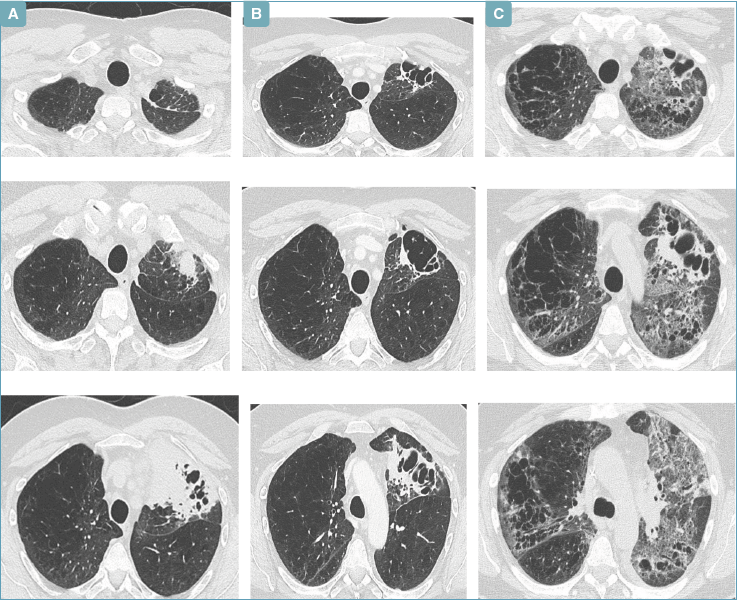

Le cellule neoplastiche mostravano una espressione di programmed death-ligand 1, ligando di morte cellulare programmata-1 (PDL1 = 3%), negative per anaplastic lymphome kinase – chinasi del linfoma anaplastico (ALK) e next generation sequencing (NGS) su DNA negativo. Trattato presso l'Oncologia del nostro ospedale con quattro cicli, ben tollerati, di carboplatino, pemetrexed e pembrolizumab dal 08/2023 al 10/2023 ottenendo una regressione parziale della neoplasia (Fig. 1). Secondo i criteri RECIST: diminuzione del 30% nella somma dei diametri delle lesioni target, rispetto alla valutazione basale.

Cinque giorni dopo l’inizio dell’antibioticoterapia, per la persistenza dei sintomi, durante una visita ambulatoriale oncologica nel nostro ospedale il paziente presentava importante desaturazione a riposo (SpO2 86% in aria ambiente). Eseguiva esami ematochimici che mostravano lieve anemia (Hb 11,6 g/dL; vn 13,5-18 g/dl; eritrociti 4.020.000/mm3; vn 420.000.000-600.000.000/mm3), globuli bianchi (9.520/mm3; vn 4.000-10.000/mm3), piastrinosi (603.000/mm3; vn 150.000-400.000/mm3) aumento della concentrazione sierica di LDH (419 U/L vn < 248 U/L) con procalcitoninemia (PCT) nei limiti di norma (0,21 ng/mL vn 0,00-0,50 ng/ml). Veniva, pertanto, eseguita una TC torace urgente con contrasto che evidenziava la presenza di opacità parenchimali polmonari diffuse e bilaterali maggiori a sinistra (Fig. 1).

Figura 1.Pannelli di TC torace: a) al momento della diagnosi dell’adenocarcinoma polmonare primitivo; b) dopo i 7 cicli di chemio-immunoterapia; c) dopo la visita in day hospital oncologico subito prima del ricovero.